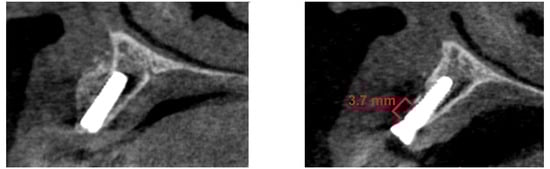

2.4. Bone Loss and Radiological Bone Measurements